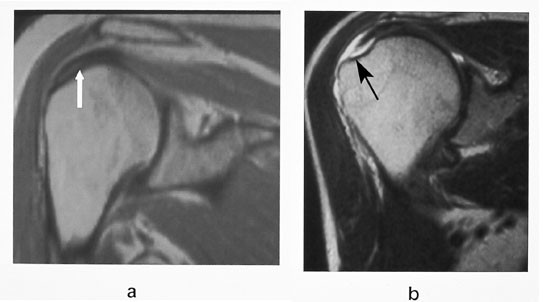

Rotatorcuffruptur er en samlingsbetegnelse på ruptur av senene til en eller flere av de fire rotatorcuffmusklene. Hyppigst forekommer ruptur av supraspinatussenen, fordi blodforsyningen til muskel-sene-overgangen er dårlig (fig 10). Diagnose av ruptur er den samme som for ligamenter ellers. Partielle rupturer fra undersiden kan være vanskelig å diagnostisere ved MR. MR-artrografi vil vise kontrastutsiving inn i senen fra undersiden. Trange forhold for m. supraspinatus og sene lar seg lett diagnostisere ved en skrå sagittal sekvens. Da får man fremstilt den akromio-klavikulære buen på en ideell måte. Det skal bemerkes at det er andre årsaker til såkalt innklemmingssyndrom enn trange forhold, som for eksempel periartikulære ganglier (fig 11).

Ved spørsmål om instabilitet eller residiverende luksasjoner, utføres en MR-artrografi. Man ser etter forandringer i labrum, fossa glenoidalis, kapsel med ligamenter og caput humeri. I tillegg til de vanlige projeksjonene utføres også en såkalt ABER (abduksjon ekstern rotasjon)-projeksjon (9) (fig 12). Pasienten ligger med armen rotert over hodet. Snittene legges parallelt med lengdeaksen av humerusdiafysen. De fremre strukturer blir dermed lagt i strekk og patologiske forhold blir synlige (fig 12).